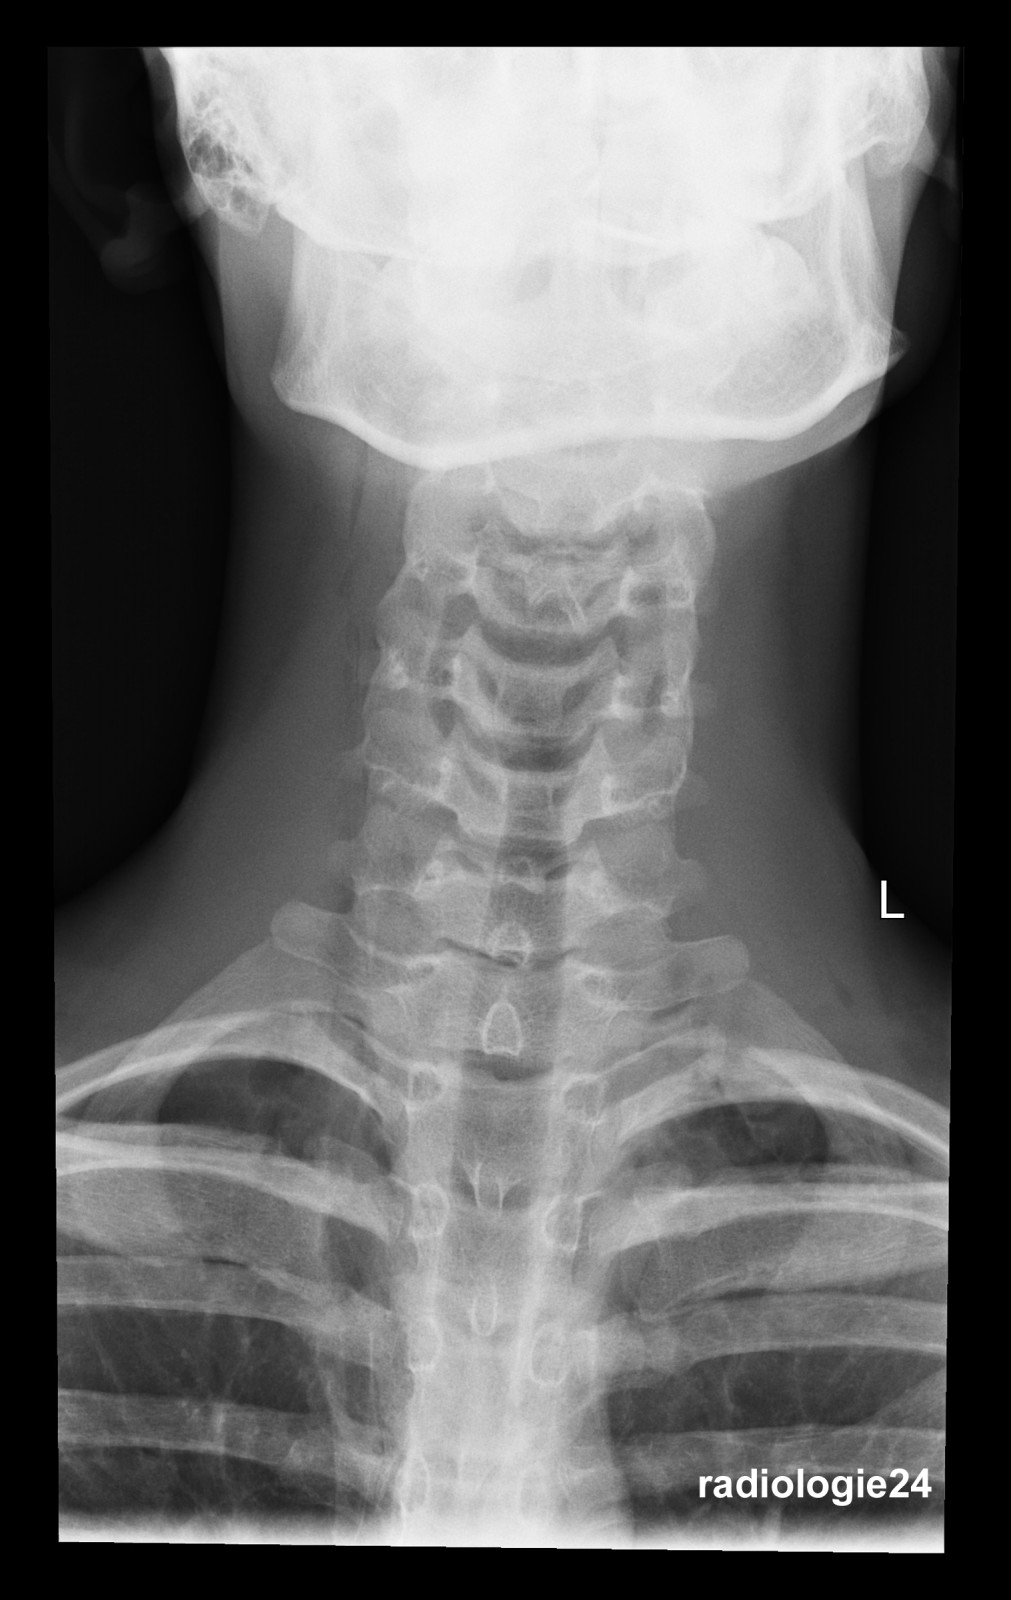

Röntgenfall des Monats Januar 2018 mit Auflösung

17 jähriger Patient

Sturz auf den Rücken beim Crossbiken. Schmerzen HWS und Thorax.

Fraktur, Pneumothorax, andere Pathologien?

Weitere bildgebende Diagnostik? Welche? Warum?